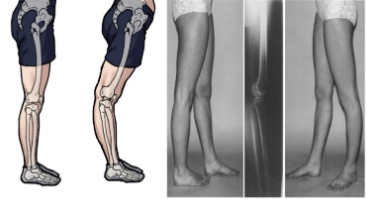

2. 과도한 무릎 펴짐 (반장슬)

- 무릎 관절은 정상적인 가동 범위 내에서 굽힘과 펴짐이 가능하다.

그러나 무릎이 과도하게 펴지는 '반장슬' 체형이 있다.

이 경우 무릎이 펴질 때 다리가 안쪽으로 회전하게 된다.

3. 반장슬 체형의 원인

- 하체 근육의 불균형: 무릎 주변 근육의 힘 균형이 깨져 과도한 펴지는 현상이다.

- 선천적 인대 느슨함: 인대가 느슨해져 무릎이 과도하게 펴지는 경우이다.